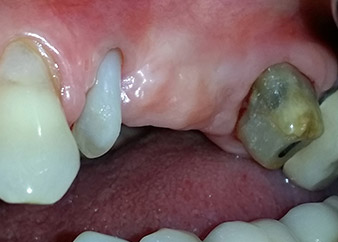

Un mese più tardi, nel giorno programmato per l'intervento, il dolore e l'infiammazione in corrispondenza del dente 24 erano minimi, ma era ancora presente mobilità di classe 2 secondo Miller. Dopo l'apertura dei lembi e la pulizia del tessuto periapicale e periradicolare infetto, l'estensione della mancanza ossea si è resa evidente (Figg. 2 e 3).

Tutto il tessuto osseo vestibolare e distale era mancante in corrispondenza della radice buccale. La possibilità di attacco era essenzialmente ristretta alla radice palatale, evidenziando la prognosi negativa preliminare. Anche il dente 27 mostrava un punto di attacco orizzontale ridotto e una rarefazione apicale minima (cfr. Fig. 1), senza sintomi clinici.

Si è mantenuta , tuttavia, l'idea iniziale di conservare entrambi i denti come appoggi temporanei del ponte durante il periodo di sei mesi per l'osteointegrazione degli impianti. In seguito la situazione si sarebbe assestata. In primo luogo, in un tentativo di risolvere il problema entro-periodontale, la superficie radicolare rimanente è stata attentamente sbrigliata con apparecchiatura piezoelettrica (Piezomed di W&H con l'attacco S1 a spatola, progettato in origine per l'erosione della parete laterale del seno mascellare) Fig. 4).